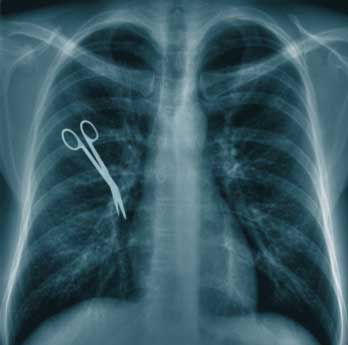

Una definición válida podría ser: La actuación de un profesional de la medicina que se desvía de los estándares normalmente aceptados por la Comunidad Médica, con un resultado lesivo para el paciente que puede llegar hasta la muerte.

Por lo dicho, la mera presencia de un resultado lesivo no supone una práctica negligente sino que se debe demostrar la conducta médica anómala. Dicho de otra manera: a la Ciencia Médica, en su actual estado de desarrollo, se le exige "obligación de medios no de resultados", salvo en ciertas actuaciones médicas como podría ser el caso de los procedimientos de Cirugía Plástica y Reparadora. La determinación de la existencia de una negligencia por parte del Tribunal que estudie el caso llevaría aparejada una indemnización por los daños ocasionados, con la finalidad de paliar, al menos en parte, el perjuicio sufrido en la salud a resultas de ésta.

La conducta reprochable del médico (imprudencia), la existencia de un daño y la relación causal entre ambos (conducta y daño) constituyen los elementos de la negligencia médica.